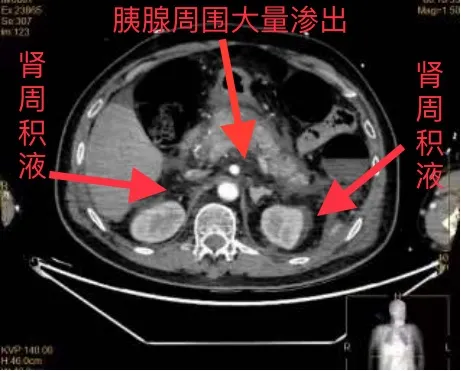

CT检查发现,廖爷爷胰腺周围大量渗出,双侧肾周积液,被确诊为重症急性胰腺炎